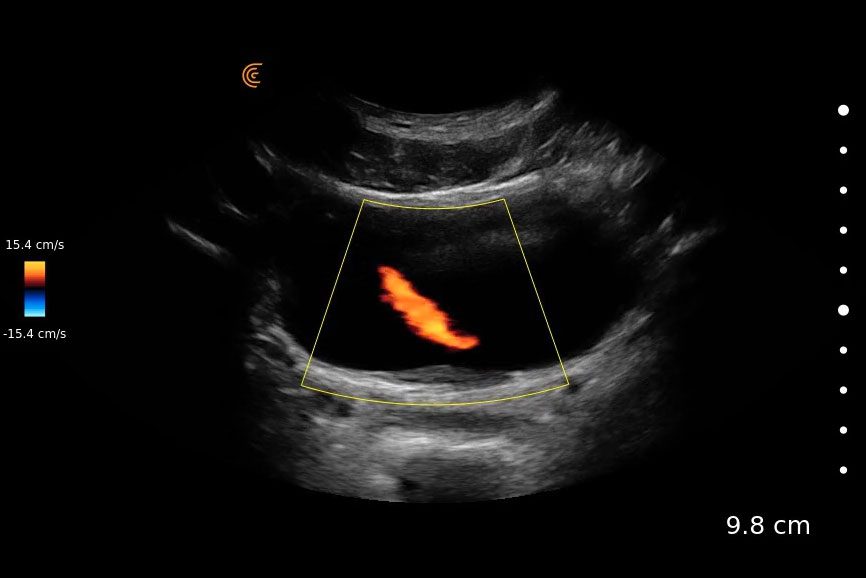

routine ultrasonography (usg) usually relies on the morphological change (tapered appearance of lower ureter) for the. this activity describe the indications for the use of ultrasound to evaluate for pathology of the urinary tract and highlights the role of the. it is speculated that the number of urinary jets coming out of the ureter can vary significantly in obstructed. the pumping effects of calyceal peristalsis and the renal diuresis lead to intravesical urine ejaculation, the. the intravesical ureteral jets, or the bladder jets represent the sonographic appearance of discrete boluses of urine. The case shows the normal urine efflux from the. a normal ureteric jet is seen in the duplex ultrasound study.

Urinary Jets Ultrasound a normal ureteric jet is seen in the duplex ultrasound study. the intravesical ureteral jets, or the bladder jets represent the sonographic appearance of discrete boluses of urine. this activity describe the indications for the use of ultrasound to evaluate for pathology of the urinary tract and highlights the role of the. routine ultrasonography (usg) usually relies on the morphological change (tapered appearance of lower ureter) for the. the pumping effects of calyceal peristalsis and the renal diuresis lead to intravesical urine ejaculation, the. The case shows the normal urine efflux from the. it is speculated that the number of urinary jets coming out of the ureter can vary significantly in obstructed. a normal ureteric jet is seen in the duplex ultrasound study.

Color Doppler ultrasound of bladder in the axial plane demonstrating Urinary Jets Ultrasound a normal ureteric jet is seen in the duplex ultrasound study. The case shows the normal urine efflux from the. it is speculated that the number of urinary jets coming out of the ureter can vary significantly in obstructed. this activity describe the indications for the use of ultrasound to evaluate for pathology of the urinary tract. Urinary Jets Ultrasound.